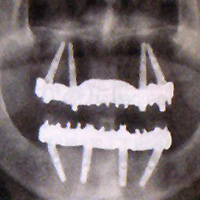

インプラント治療とは、歯が抜けてしまった部分にインプラント(人工歯根)を埋めて顎の骨と結合させ、その上から人工歯を被せる歯科治療です。咬み心地も快適で、人工歯の色調や形などは自然歯に合わせることができます。歯科医療における最先端技術で、天然歯と同等の機能性や見た目を手に入れることができます。

総入れ歯の方対象のクイック・インプラントシステム『オールオン4』は、4本のインプラントで片顎12〜14本の歯を支えるインプラント治療法で、従来よりも本数が少なく済むことや、即日食事が可能になるなどの特徴があり、経済的・身体的侵襲ともに少なくなります。本当に必要とされている方に自信をもっておすすめします。